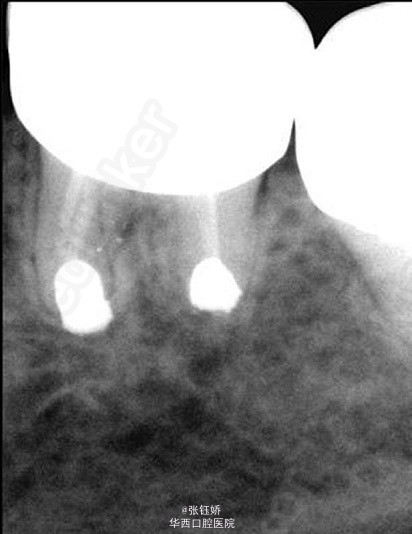

女,56岁,自觉左下磨牙区敏感不适,X线片示36牙已根充,远中根管超填,近中根管欠填,根管预备显示近中根管下段钙化,根尖周见较大暗影。考虑到患者牙合间距离很小不符合根尖手术适应症,故拟行意向性牙再植术。